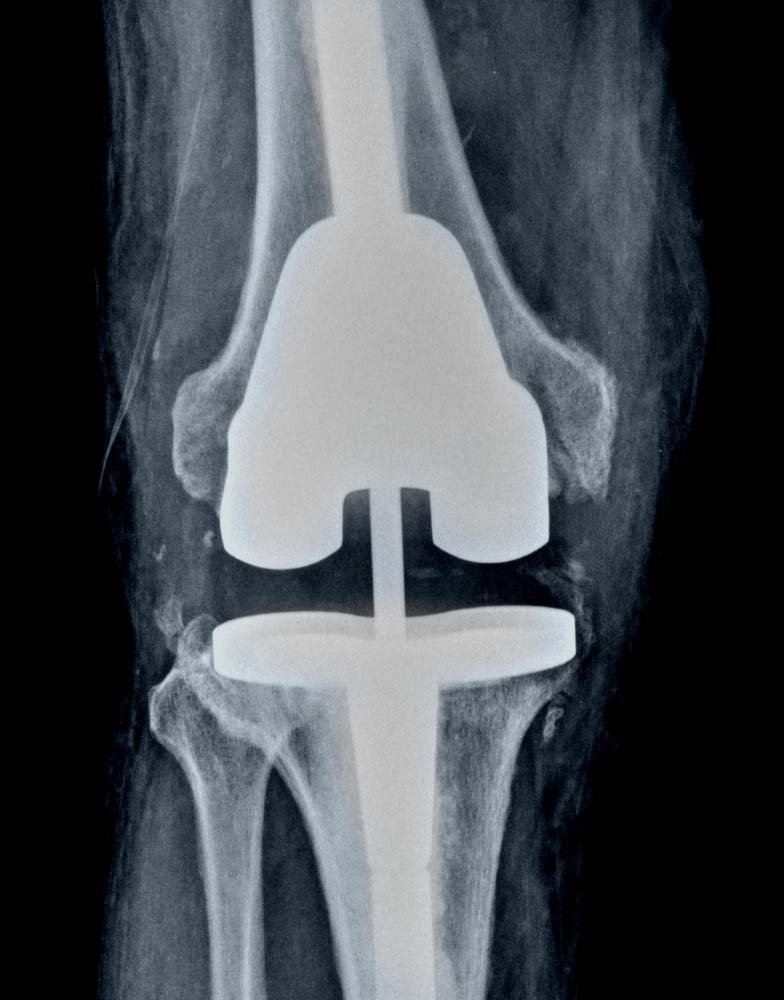

If your knee replacement fails, Dr. Jay Shah may recommend that you have a second surgery—revision total knee replacement. In this procedure, Dr. Jay Shah removes some or all of the parts of the original prosthesis and replaces them with new ones.

Dr. Jay Shah will examine the soft tissues in your knee to make sure that they are free from infection. He will assess all the metal and/or plastic parts of the prosthesis to determine which parts have become worn or loose or shifted out of position.

After removing the original implant, the doctor will prepare the bone surfaces for the revision implant. In some cases, there may be significant bone loss around the knee. If this occurs, metal augments and platform blocks can be added to the main components to make up for the bony deficits.

Finally, the doctor inserts the specialized revision implant, repairs any surrounding soft tissues that are damaged, and carefully tests the motion of the joint. A drain may be placed in your knee to collect any fluid or blood that may remain after surgery.